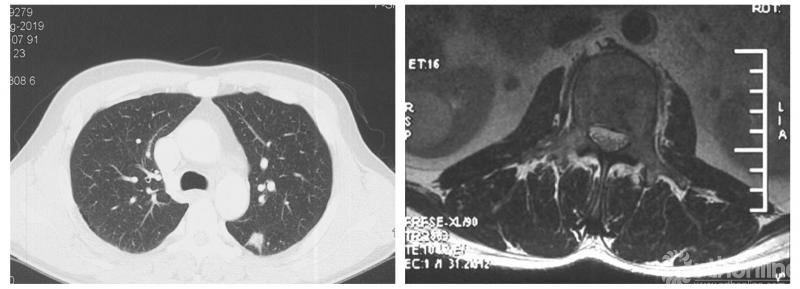

患者房某,男性、51岁。主因“腰痛3个月”入院,既往外院诊断“周围型肺腺癌”,全身检查提示多发骨转移。

经Spine Oncology Study Group(SOSG)评估硬膜外脊髓压迫(ESCC)为Grade 1a型,轻度脊髓压迫;脊柱机械稳定性评估(SINS)7分,中度不稳。修正Tokuhashi评分(RTS)6分,预计生存<6个月,建议姑息性手术及保守治疗;结合Tomita评分系统6分,故行姑息性手术短期控制。

影像学资料

PVP治疗

术后6个月